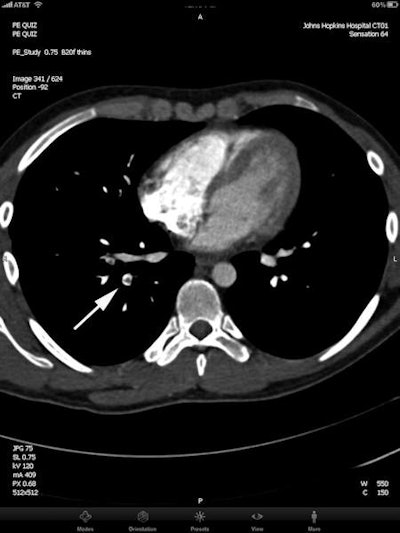

| Axial image (top) and sagittal multiplanar reconstruction (bottom) from contrast-enhanced MDCT viewed on the iPad. Arrows show right lower lobe segmental pulmonary embolism. All images courtesy of Dr. Pam Johnson. |